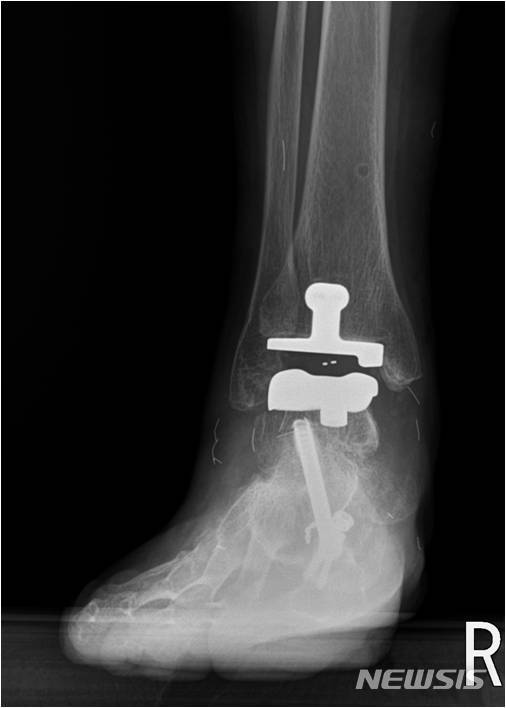

발목 인공관절 수술 후

발목 인공 관절 수술을 할 때 가장 중요한 것은 운동입니다.이는 재발 방지 및 복구 단계를 통해 재발 방지 및 복구 단계를 통해 신속하게 복구 단계를 신속하게 복구할 수 있습니다.발목 인공 관절 수술은 많지만 무릎 관절과 힙합 관절과 힙합 관절에 비해 높은 고장률이 높기 때문에 주의해야 한다.또한 인공 관절 수술 실패 후 다양한 발 관절질환 치료 실패 이후 치료의 지식은 중요하다.#아 인공 관절 수술